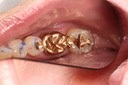

Frank Fukuda #19 caries removal

Frank Fukuda #19 caries removal buccal